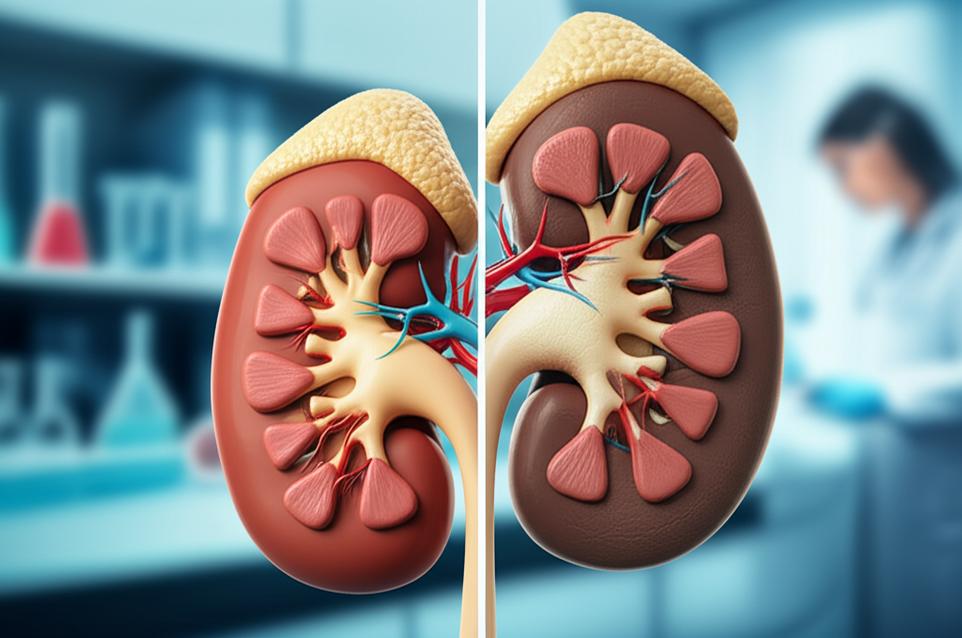

กลไกการทำงานของไตและการเสื่อมสภาพตามวัยในมุมเวชศาสตร์ชะลอวัย

ไตแต่ละข้างประกอบด้วยหน่วยไตเล็กๆ นับล้านหน่วยที่เรียกว่า “เนฟรอน” ทำหน้าที่กรองเลือด ขับของเสีย และรักษาสมดุลของสารต่างๆ ในร่างกาย เมื่ออายุเพิ่มขึ้นหรือจากการเผชิญกับปัจจัยกระตุ้น เนฟรอนเหล่านี้จะค่อยๆ เสื่อมประสิทธิภาพลงและลดจำนวน ทำให้ความสามารถในการกรองของเสียลดลง และเกิดการสะสมของสารพิษ ซึ่งเป็นที่มาของภาวะไตเสื่อม ในมุมมองของเวชศาสตร์ชะลอวัย การเสื่อมของไตไม่ได้เป็นเพียงกระบวนการธรรมชาติที่หลีกเลี่ยงไม่ได้ แต่ยังมีปัจจัยหลายอย่างที่เร่งให้เกิดความเสื่อมเร็วขึ้น อาทิ:

การทำความเข้าใจกลไกเหล่านี้ทำให้เราสามารถออกแบบแนวทางการดูแลที่มุ่งเน้นการแก้ไขที่ต้นเหตุ เพื่อฟื้นฟูและประคับประคองการทำงานของไตได้อย่างยั่งยืน